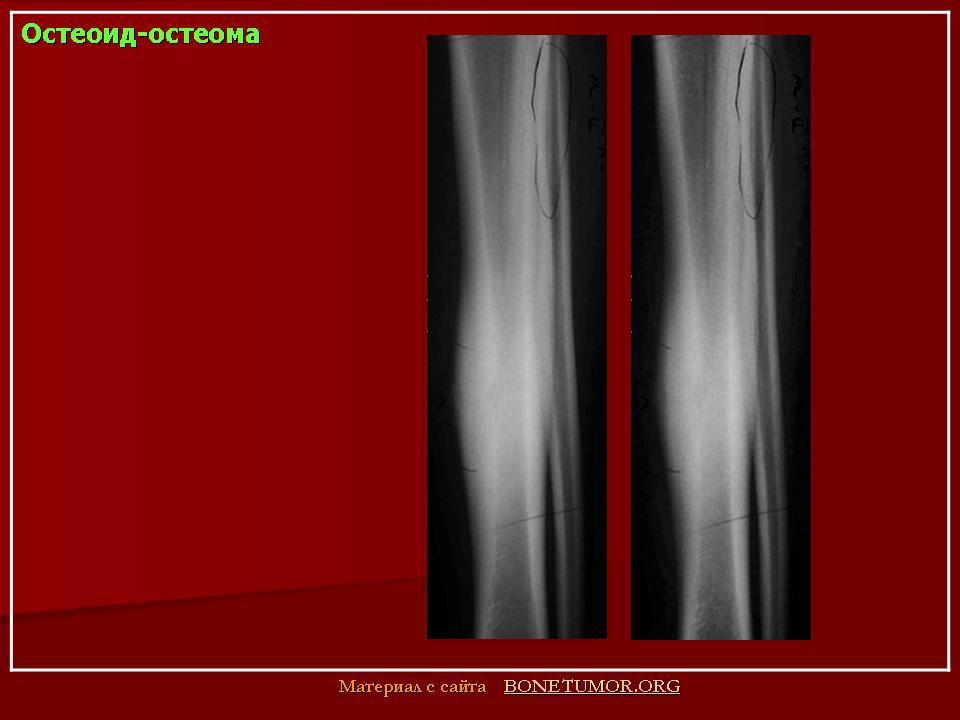

Рентгенологическая картина остеоид-остеомы весьма характерна. Рентгенологические симптомы возникают значительно позже клинических проявлений опухоли, и первым на рентгенограмме обнаруживают склероз кости. На участке поражения формируется одностороннее или муфтообразное утолщение кости в виде гиперостоза. Позднее в толще гиперостоза формируется основной отличительный признак остеоид-остеомы - ее «гнездо» в виде очага разрежения диаметром до 1 см, внутри которого могут отмечаться мелкие костные включения. Сквозь слой склерозированной ткани «гнездо» опухоли на обычных рентгенограммах не всегда дифференцируется и для ее выявления применяют лучи повышенной жесткости и томографию. Обнаружение «гнезда» необходимо для подтверждения диагноза и проведения направленного оперативного вмешательства.